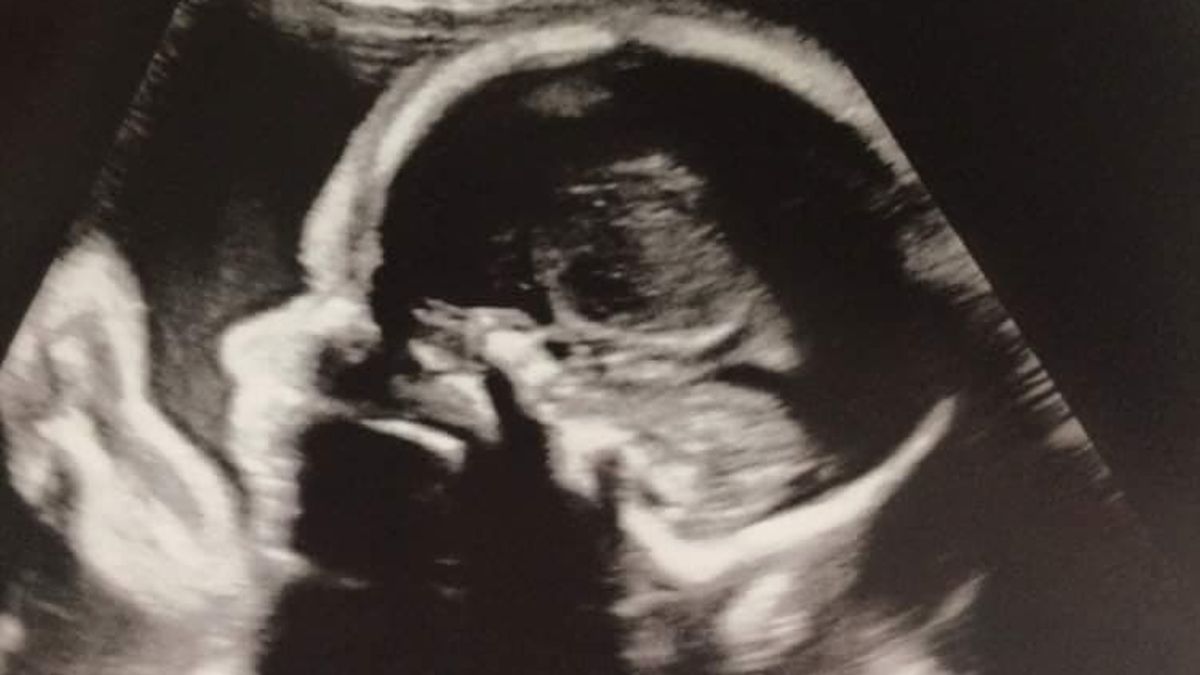

Mi vejiga parece bastante ordenada. Se podían ver sombras leves, pero nada que indicara que la placenta está en una etapa demasiado avanzada y está penetrando mi vejiga. Algo que me tranquiliza. Porque la imagen que los médicos vieron en la ecografía ya era bastante extrema para un término de 17 semanas. Con bastante calma, salgo al exterior y decido hacer inmediatamente una visita al baño. Dato curioso: la sensación más antinatural, pero agradable que he experimentado hasta ahora allí abajo. El líquido que fue introducido en mi vejiga naturalmente tenía que salir. Apuesto a que no muchos de ustedes han experimentado alguna vez una orina helada. Refrescante, de hecho...

Las palabras resuenan. La placenta no está ni adherida ni fusionada. No, la placenta está completamente atravesada... Una imagen que es muy alarmante para esta etapa del embarazo. Y entonces llegaron las peores noticias. Palabras que resonarán para siempre. “Ahora tenemos que consultar con los líderes de opinión clave en esta patología si es seguro continuar con el embarazo, o si debería terminarse lo antes posible”. Terminar, terminar, terminar...